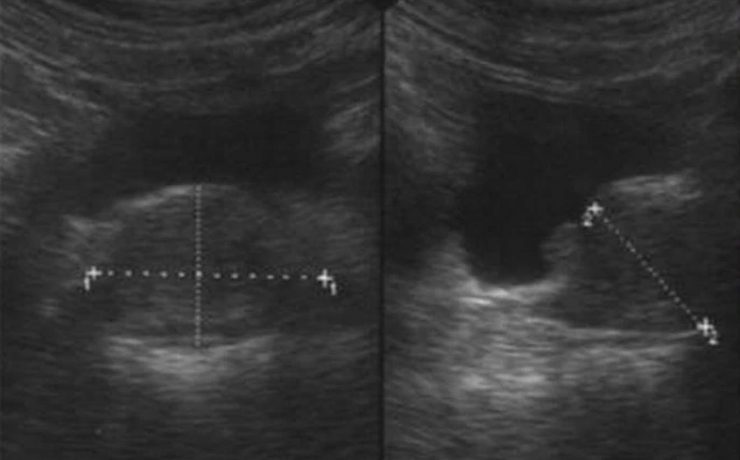

Hiperplasia prostática benigna

La hiperplasia prostática benigna (HPB) es muy prevalente en atención primaria; es el principal motivo de consulta por problemas urológicos en el hombre y es el primer diagnóstico que debemos pensar ante un paciente mayor de 50 años que consulta por síntomas obstructivos y/o irritativos. El diagnóstico de HPB es